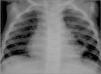

En la exploración física destaca buen estado general, leve tiraje subcostal y polipnea, con buena entrada de aire bilateral y espiración alargada. La paciente se mantiene afebril y presenta una saturación de hemoglobina (Hb) del 90 %. Tras contactar con el Instituto Nacional de Toxicología, se administra carbón activado (20g) por sonda nasogástrica. Se practica radiografía de tórax y se observan infiltrados alveolares bibasales (fig. 1), analítica general, que es normal, y gasometría venosa, que muestra leve acidosis respiratoria (pH 7,31; pCO2 49,7mmHg; pO2 38,6mmHg; bicarbonato 25mEq/l; EB −1,6mEq/l). Dado el antecedente de la intoxicación seguida de vómitos y la imagen radiológica, se orienta como neumonía lipoidea exógena. Se decide ingreso y se inicia tratamiento con oxígeno suplementario en cánulas nasales, antibioticoterapia intravenosa profiláctica con amoxicilina-ácido clavulánico y corticoterapia intravenosa con metilprednisolona (1mg/kg/día). A las 24h del ingreso se realiza tomografía computarizada (TC) pulmonar. Se evidencian imágenes de condensación pulmonar con patrón alveolar en lóbulo medio, língula y ambos lóbulos inferiores, sin observar alteraciones en lóbulos superiores, imágenes de tipo necrótico o bullas (fig. 2).

La sintomatología inicial se caracteriza, al igual que otras neumonías aspirativas, por tos, dificultad respiratoria y dolor torácico, pudiendo presentar fiebre o en ocasiones escasez de síntomas1,3. El primer caso descrito presentaba mínima sintomatología, mientras que el segundo empezó con dificultad respiratoria progresiva y fiebre. Habitualmente, en la radiografía simple de tórax se observan infiltrados alveolares en uno o varios lóbulos, principalmente en zonas declives2,3, e imágenes “en vidrio deslustrado”. La TC puede mostrar condensación alveolar o imágenes de complicaciones pleuropulmonares como neumatoceles, nódulos fibróticos, derrames pleurales paraneumónicos, abscesos pulmonares o fístulas broncopleurales6,7. Como se puede observar en las imágenes, nuestro primer caso presentó una radiología típica sin complicaciones pleuropulmonares, mientras que el segundo desarrolló neumatoceles bilaterales que se resolvieron espontáneamente. Esta diferente evolución podría deberse a la distinta composición de la sustancia aspirada, al ser probablemente más lesivo el insecticida. En los casos con escasa clínica, debe realizarse un lavado broncoalveolar, donde se observan macrófagos cargados de lípidos en su interior, lo cual confirma el diagnóstico de neumonía lipoidea1,3,5. En nuestros pacientes no se realizó lavado broncoalveolar al considerar el antecedente de aspiración de sustancia lipídica y la clínica compatibles con el diagnóstico.